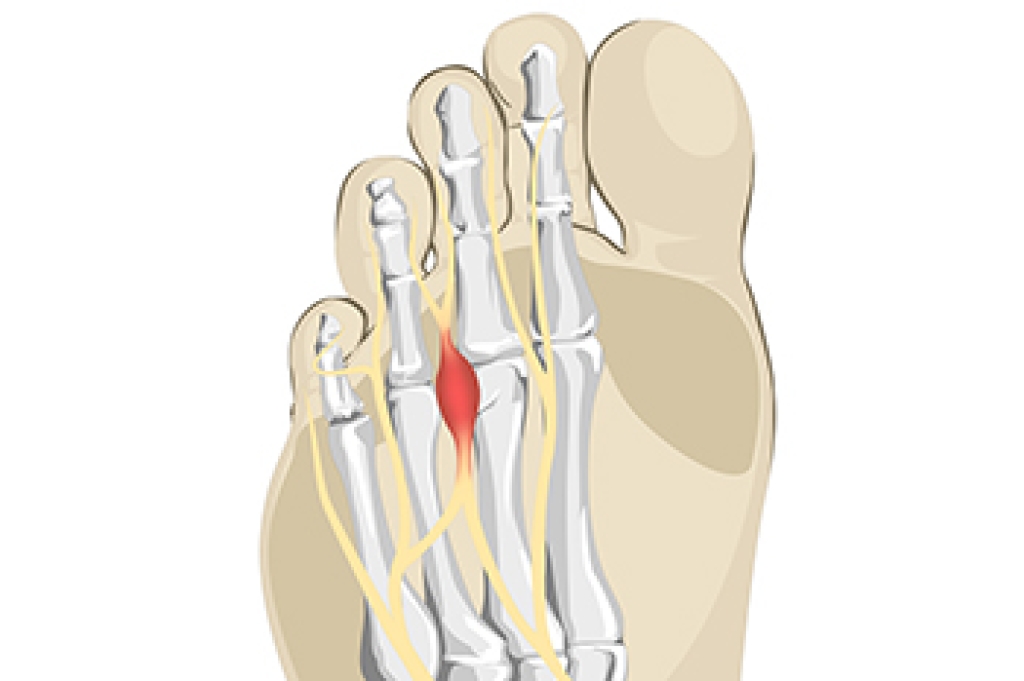

Pain From Morton’s Neuroma

A Morton’s neuroma refers to thickening of nerve tissue at the base of the 3rd or 4th toe. While the precise cause of this condition is unknown, it is thought to form from pressure, irritation, or injury of nerves leading to the toes. This condition can cause one to feel like there is a lump or knot near the ball of the foot, like they are walking on a pebble, or wearing socks that have become bunched up. There can be an achy, sharp, or burning pain in the ball of the foot, or tingling, numbness, or cramping in the forefoot or toes. A Morton’s neuroma can become swollen and painful. One can develop a Morton’s neuroma from wearing shoes that are too narrow where the toes are squeezed together or high-heeled shoes where the body weight is forced onto the ball of the foot. Non-invasive treatments for Morton’s neuroma include wearing properly fitted shoes, with heels less than two inches in height, wide toe boxes, and thick soles, using padding in shoes to take the pressure off the nerve, or taping the feet to redistribute body weight and ease inflammation. Medication and injections can also help relieve pain and pressure of this ailment. Custom orthotics can be made to provide support if one has an abnormal foot structure, such as flat feet or overlapping toes causing the condition. Surgery can be performed if a Morton’s neuroma becomes large or fails to be relieved with more conservative treatment options. Left untreated, a Morton’s neuroma can become worse. For this reason, it is suggested that you visit a podiatrist for a proper diagnosis and treatment that fits the severity of your specific foot problem.

Morton’s neuroma is a very uncomfortable condition to live with. If you think you have Morton’s neuroma, contact one of our podiatrists of Pennsylvania Foot & Ankle. Our doctors will attend to all of your foot care needs and answer any of your related questions.

Morton’s Neuroma

Morton's neuroma is a painful foot condition that commonly affects the areas between the second and third or third and fourth toe, although other areas of the foot are also susceptible. Morton’s neuroma is caused by an inflamed nerve in the foot that is being squeezed and aggravated by surrounding bones.

What Increases the Chances of Having Morton’s Neuroma?

- Ill-fitting high heels or shoes that add pressure to the toe or foot

- Jogging, running or any sport that involves constant impact to the foot

- Flat feet, bunions, and any other foot deformities

Morton’s neuroma is a very treatable condition. Orthotics and shoe inserts can often be used to alleviate the pain on the forefront of the feet. In more severe cases, corticosteroids can also be prescribed. In order to figure out the best treatment for your neuroma, it’s recommended to seek the care of a podiatrist who can diagnose your condition and provide different treatment options.